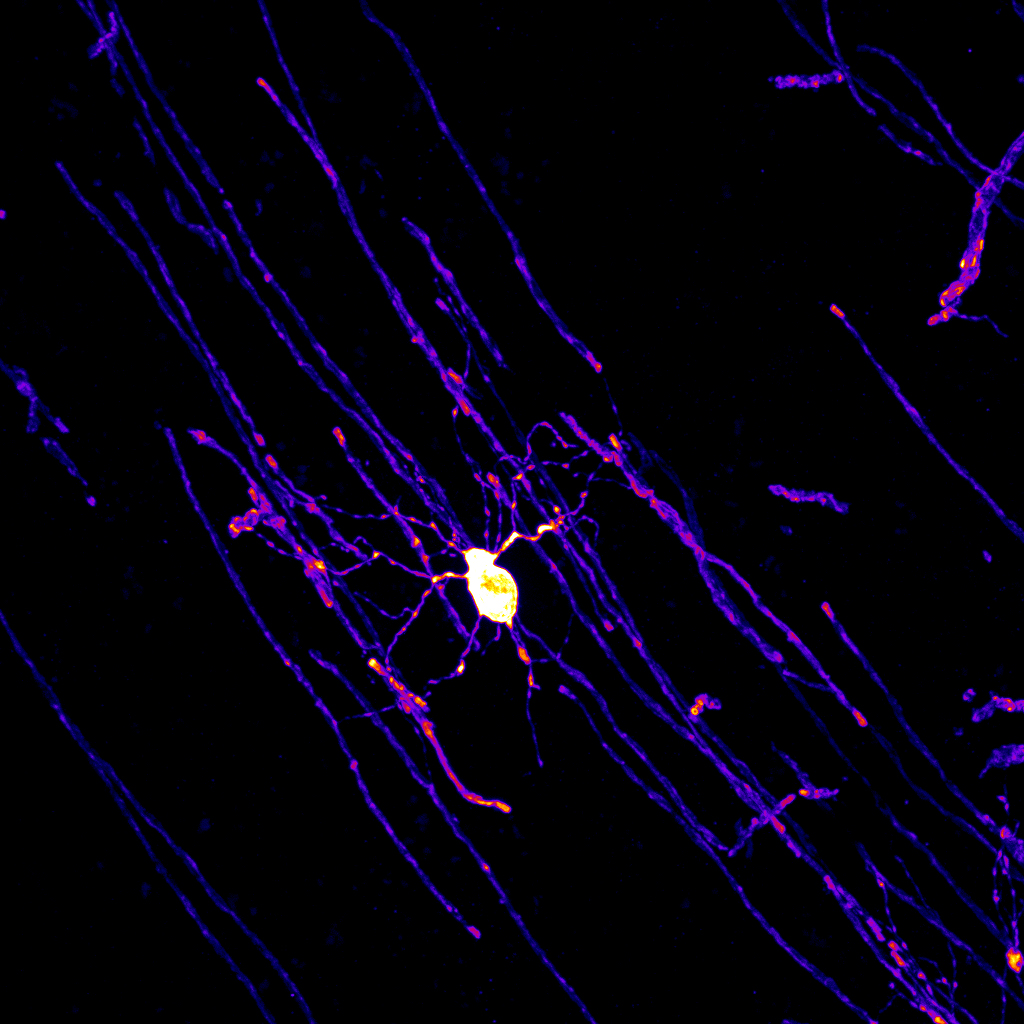

Der Wachstumsfaktor Erythropoietin (EPO), bekannt aus der Blutbildung, hat auch wichtige Effekte im Gehirn – insbesondere auf sogenannte Oligodendrozyten. Diese Zellen sind zuständig für die Bildung von Myelin, der „Isolierung“ der Nervenfasern, die eine schnelle Signalübertragung ermöglicht. Die Ergebnisse der Forschenden des Max-Planck-Instituts für Multidisziplinäre Naturwissenschaften in Göttingen und des Zentralinstituts für Seelische Gesundheit in…